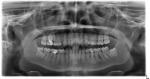

Здравствуйте! КТ не нашла где сделать, сделала панорамный снимок. Может подойдёт такой?

И мне после снимка провели небольшую консультацию, сказали, что в нескольких зубах имеется кариес (хотя месяц назад в другой клинике я вылечила 3 зуба, с остальными зубами сказали всё ок). Плюс сейчас мне сказали, что 5ка справа с глубоким кариесом до нерва, а 6ка с кистой ????????♀️ Действительно всё так плохо?

"И мне после снимка провели небольшую консультацию, сказали, что в нескольких зубах имеется кариес (хотя месяц назад в другой клинике я вылечила 3 зуба, с остальными зубами сказали всё ок). Плюс сейчас мне сказали, что 5ка справа с глубоким кариесом до нерва, а 6ка с кистой? ♀️ Действительно всё так плохо? " - Да, в целом все верно Вам сказали.

"сделала панорамный снимок. Может подойдёт такой? " - КТ будет максимально информативное.

Я искала недалеко от дома, в центре Москвы на кт цены кусаются. По этому снимку вы ничего не можете сказать по поводу моей 5ки слева?

Зуб не допломбирован до верхушки корня.

Значит нужно заново открывать и пломбировать или это не страшно и можно оставить как есть?